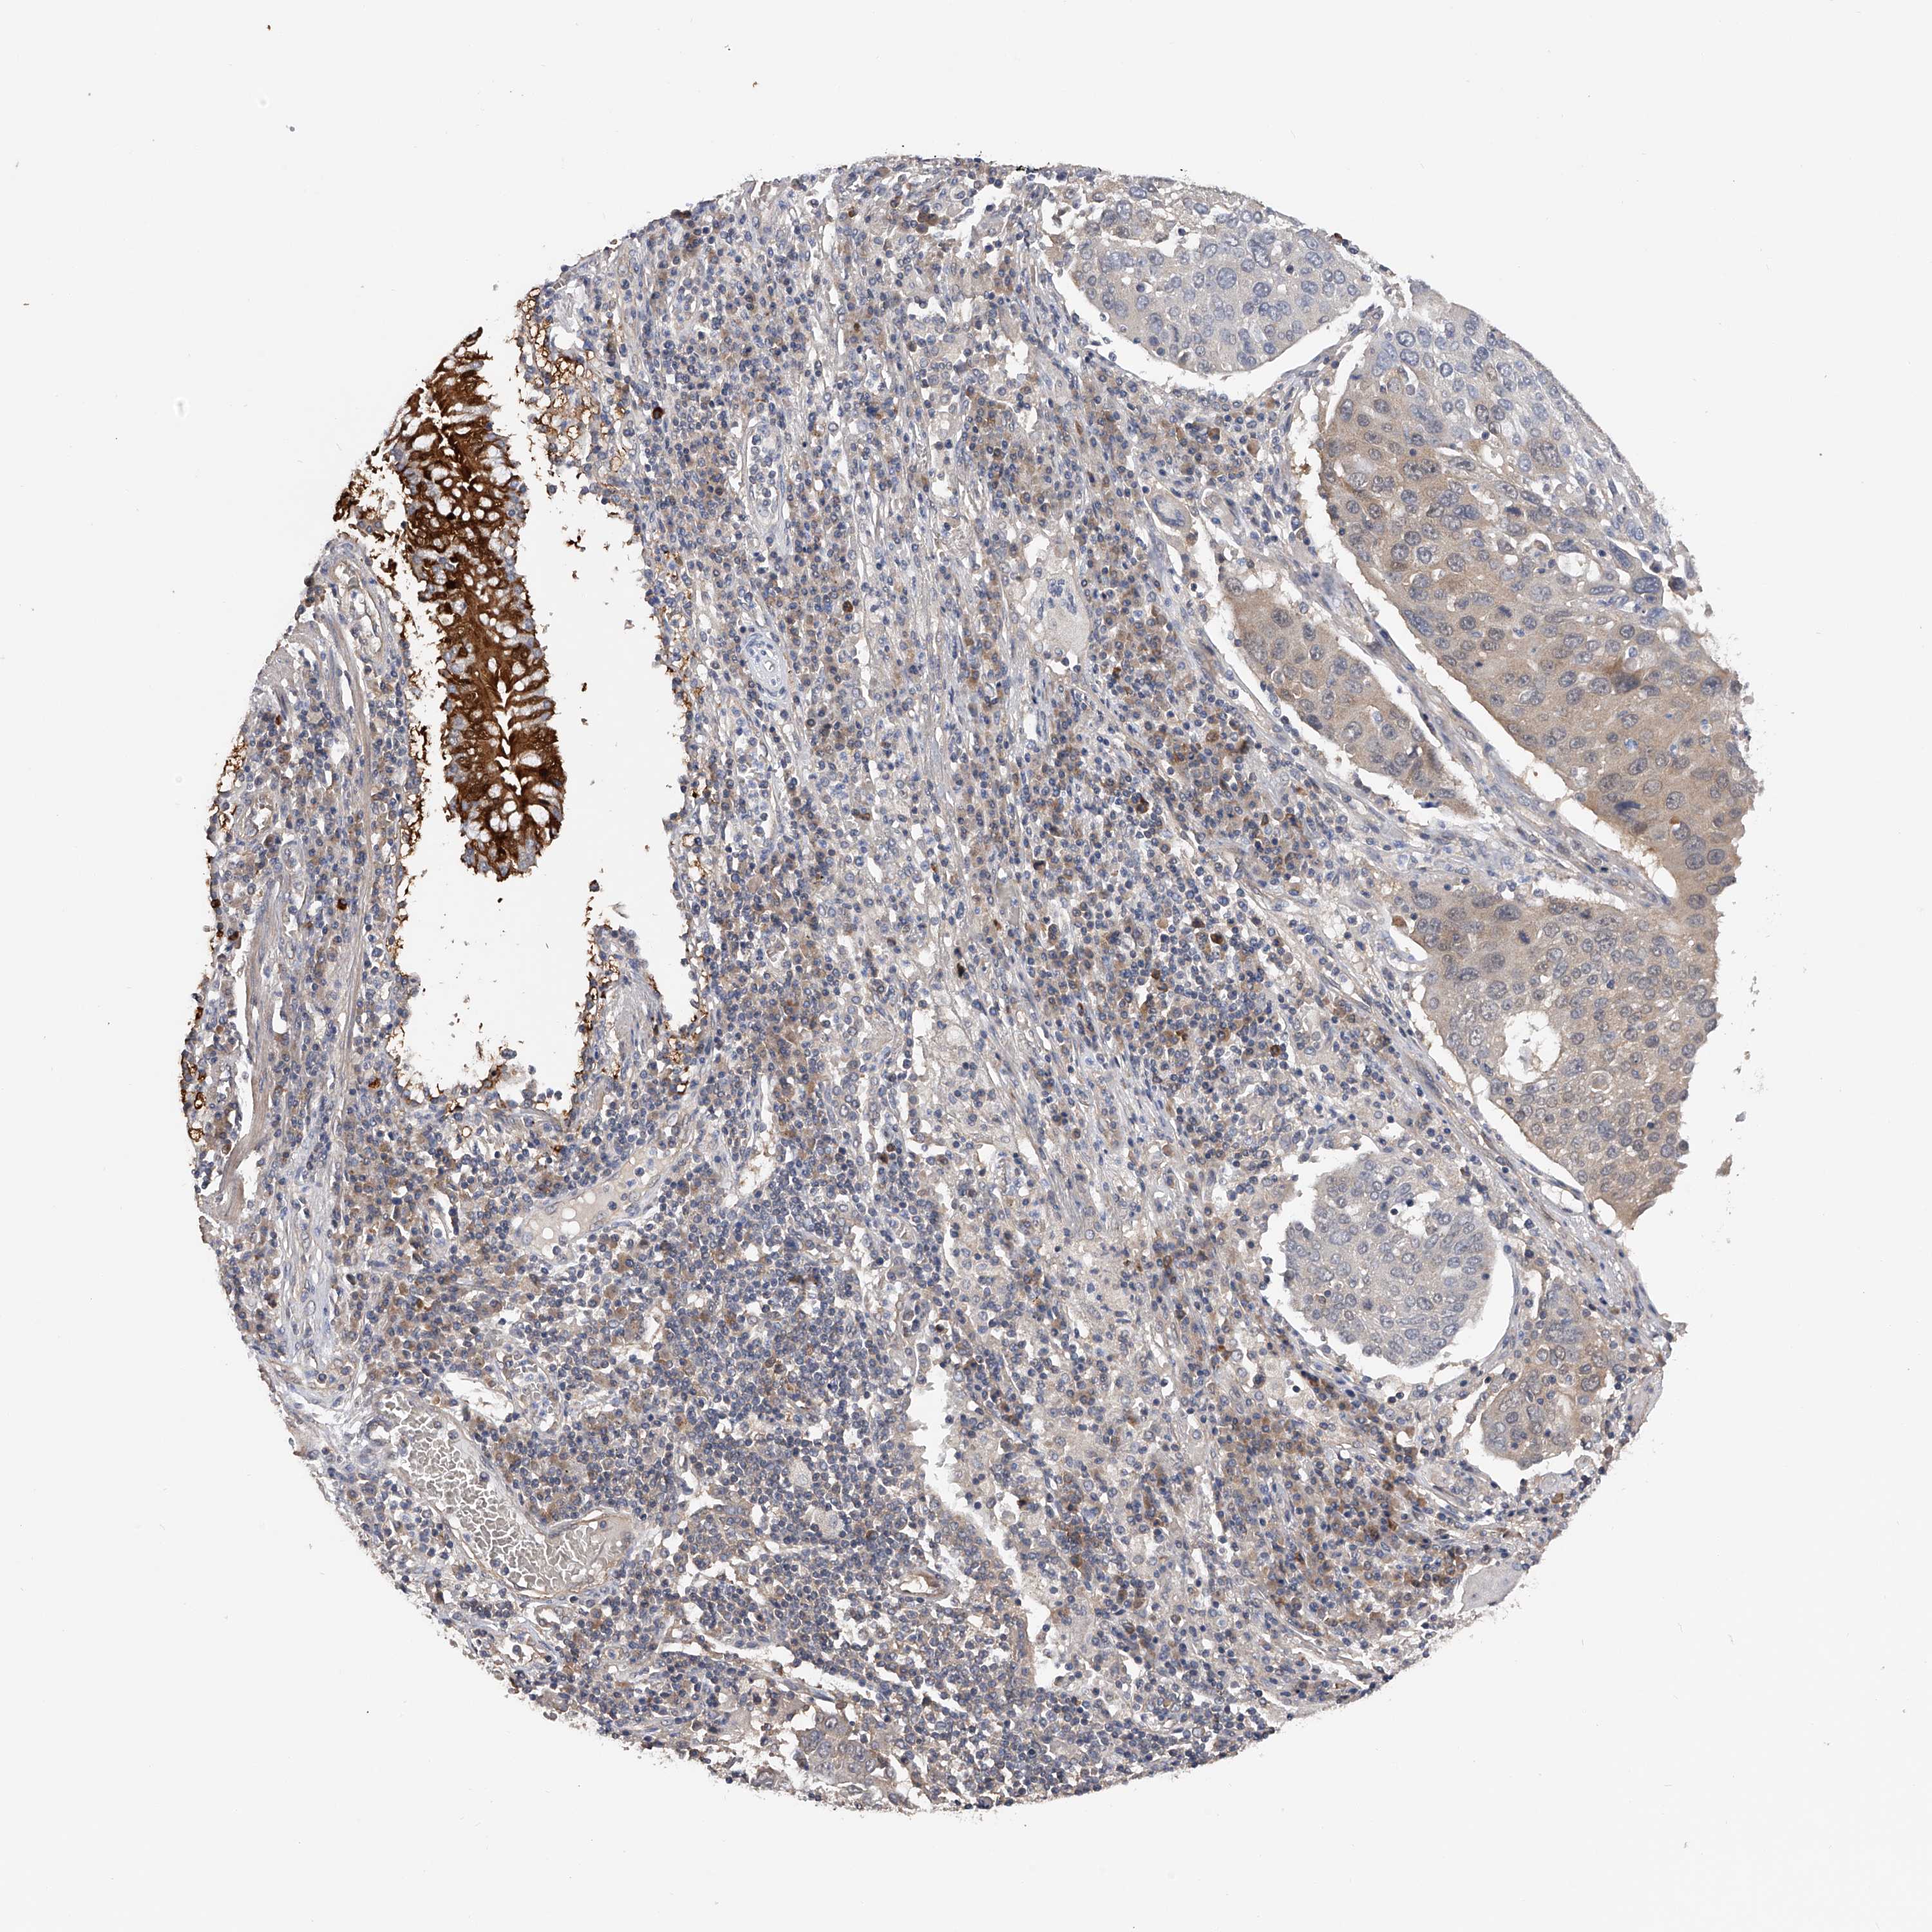

CANCER LUNG CANCER Show tissue menu

LUAD TCGA LUAD VALIDATION LUSC TCGA LUSC VALIDATION PROTEIN LUAD CPTAC PROTEIN LUSC CPTAC PROTEIN EXPRESSION

ANTIBODIES

AND

VALIDATION